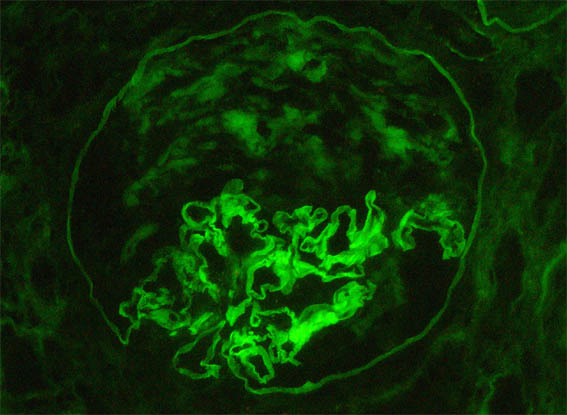

Figura 10. Otra imagen de la inmunofluorescencia directa para IgG, X400.